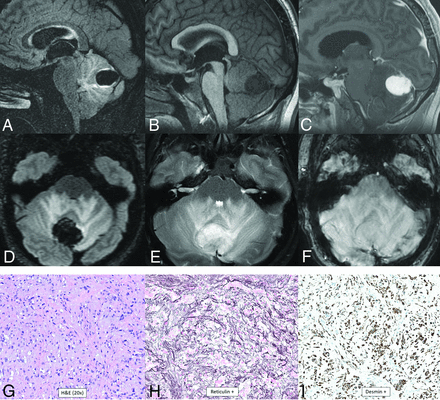

CNS tumor with BCOR internal tandem duplication. In 1 patient (A–C), there is a large well-circumscribed mass in the right posterior frontal lobe with heterogeneous T2-hyperintensity and prominent intratumoral vessels (A), heterogeneous T1-hypointensity (B), and enhancement (C, arrows). In a different patient (D–F), there is similar signal and morphology of a mass centered in the left cerebellar hemisphere on the T2-weighted (D), T1-weighted (E), and T1-weighted postcontrast (F) images (arrows). Histology from the first patient is characterized by relatively uniform nuclei, perivascular arrangement of tumor cells (rosette formation), and necrosis without microvascular proliferation (G). Immunohistochemical stains demonstrate OLIG2 positivity (H) and consistent NeuN positivity (I). Next-generation sequencing identified a frameshift mutation in BCOR, and chromosomal microarray demonstrated a segmental chromosomal loss disrupting BCOR.

CNS tumor with BCOR internal tandem duplication is a high-grade tumor that has not yet been assigned a specific WHO grade. Histologically, it is a compact tumor containing spindle and oval cells with fine chromatin with a well-demarcated border with adjacent brain parenchyma.67,70 Perivascular pseudorosettes with an ependymoma-like appearance and an intervening anuclear zone are prominent.67 Peripheral calcified palisading necrosis is typically present. Tumors often demonstrate fibrillary processes and contain dense capillary networks.67,70 GFAP and S-100 are negative, and BCOR, OLIG2, and NeuN are positive.67 Data are limited, but the reported median age is 1.8 years (range, 1.2–7.6 years) with a female predominance (male/female ratio, 1:2.3).70 Location can be supratentorial or infratentorial, but dural abutment is common. A typical tumor is large, solid, centrally necrotic, iso- to hypodense, T2-hyperintense, diffusion-restricting, and mildly enhancing. Calcification or blood products are sometimes present at the border of the necrotic region. Large intratumoral macroscopic vessels may be present (Fig 11).70